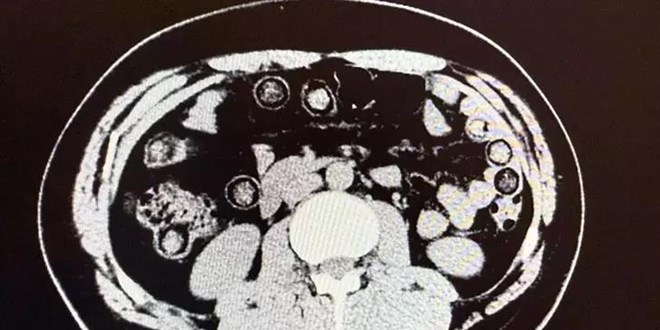

Muş Devlet Hastanesi'ne götürülen şüphelilerin yapılan kontrollerinde midelerinde uyuşturucu olduğu belirlendi.

Şüphelilerin midesinden 94 kapsül içerisinde 928 gram sentetik uyuşturucu ele geçirildi.